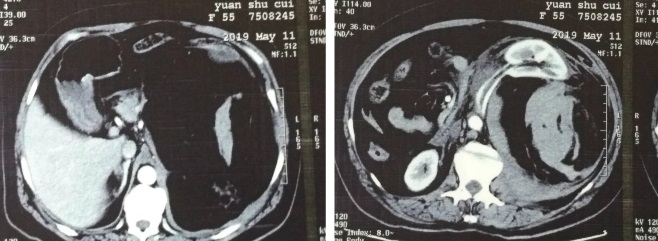

患者,女,55岁,因腹部疼痛数小时到长沙某市级医院就诊,经CT检查诊断为腹膜后肿瘤肿瘤病瘤内大出血,于5月11日下午6时紧急转入湘雅三医院,收住普外科三十四病区。刘海主任医师、杨文龙主治医师、宋智主治医师紧急查看患者,见患者有明显失血性休克表现,血红蛋白下降到7克。看阅外院CT片后,发现腹膜后肿瘤巨大(20×25厘米),并瘤内出血和腹腔出血,肿瘤包裹左侧肾脏,与脾脏、胰腺、结肠、十二指肠、腹主动脉、下腔动脉以及肠系膜血管关系密切。肿瘤累及重要的解剖结构,且合并自发性破裂出血,手术的难度很大,风险也很大,但是只有手术才能止血,也只有手术才能根治肿瘤。在与患者家人充分沟通后,手术组医生决定紧急手术治疗。在外科、麻醉科及手术相关科室的密切配合和努力下,经过数小时的惊心动魄的手术抢救,成功切除了肿瘤,使患者转危为安。

强调完整的影像学检查,如CT、MRI。要求图像清晰,以充分了解肿瘤大小、位置,与周围脏器、血管的关系,制定正确的手术方案。术前应备有充足血源,包括各种凝血因子的准备。充分准备手术器械和设备,建立大静脉通道,多采用上肢及颈静脉,可进行中心静脉压测定,一般不用下肢静脉输液,避免手术时压迫下腔静脉影响液体回流。